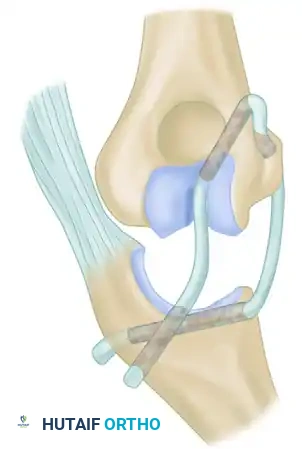

3. Ligament Reconstruction (The Arafiles Technique)

In cases of profound instability where dynamic fixation is unavailable or insufficient, surgeons may opt for ligament reconstruction with or without adjunctive fixation. The Arafiles technique utilizes a tendon graft routed through precisely drilled osseous tunnels to recreate the stabilizing vectors of the collateral ligaments.

The following sequence illustrates the complex reconstruction for an old posterior dislocation of the elbow, demonstrating the slot created in the trochlea and the specific lines of drill holes (A to D) that dictate the course of the tendon graft.

Note the intact forearm flexor origin during the completed repair, which provides secondary dynamic stability to the medial aspect of the reconstructed joint.